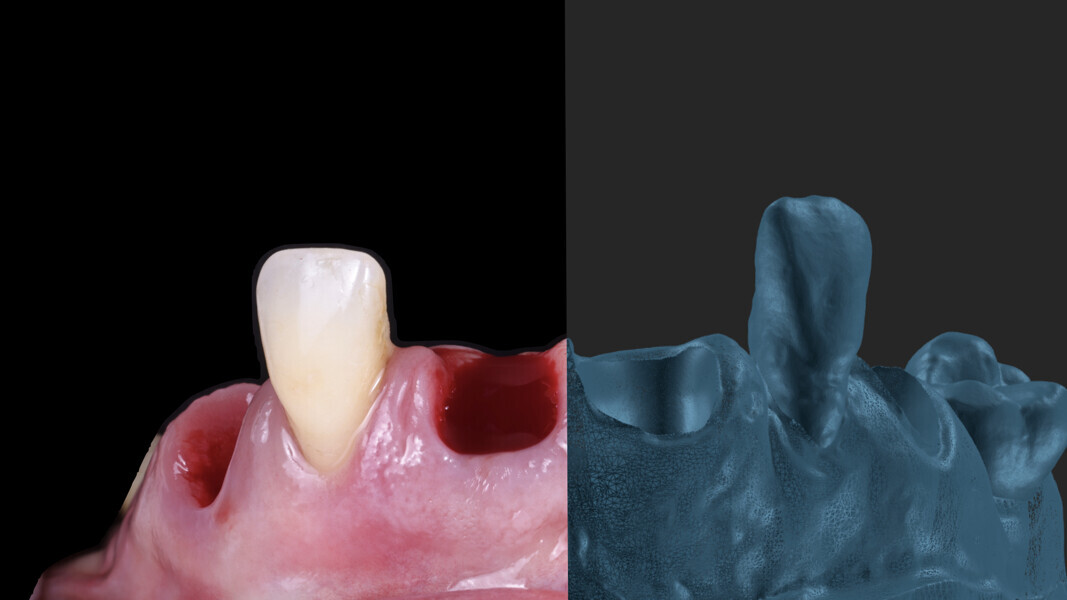

Fig. 19: Soft-tissue deficit in the area of tooth #12 that was to receive a connective tissue graft.

2. Removal of the temporary restoration: After removing the temporary restoration, we took an impression of the soft tissue underneath (Fig. 26).

3. Placement of SmartFlag scan bodies: We then placed the scan bodies and captured a digital impression with them. The positioning of these scan bodies is critical for accuracy. Designed to reduce the distance between implants, they minimise inaccuracies in digital full-arch impressions. Additionally, each scan body is marked with a specific marking that helps the dentist in scanning and helps the dental technician to identify and correct any mismatches, ensuring perfect alignment (Fig. 27). The SmartFlag scan bodies are not only incredibly efficient but also user-friendly, reducing the scanning time to just 1–2 minutes. Previously, after placing the transfer, we had to splint each implant coping with pattern resin, separate them between implants and re-splint them to avoid tension in the definitive restoration. We also needed to create holes in the impression tray to allow unscrewing of the copings and removal of the impression. In some cases, a second impression with an individualised tray from the dental technician was necessary, resulting in more chair time and additional appointments (Figs. 28 & 29). With SmartFlag scan bodies, all these complications are now eliminated. Furthermore, patients with excessive gag reflexes greatly benefit from this streamlined process because it reduces discomfort.

4. Digital impression of the temporary restoration: We also took a digital impression of the temporary restoration outside the mouth. This would be used by the dental technician to create a working model by copying the custom emergence profiles from the design and making necessary modifications for the definitive restoration (Figs. 30 & 31).